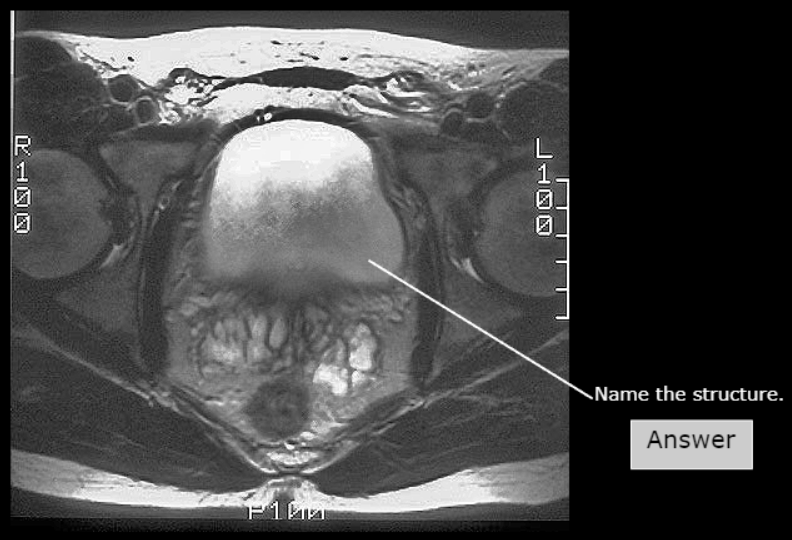

Rectum

Obturator internus

Cervix

Body of Uterus